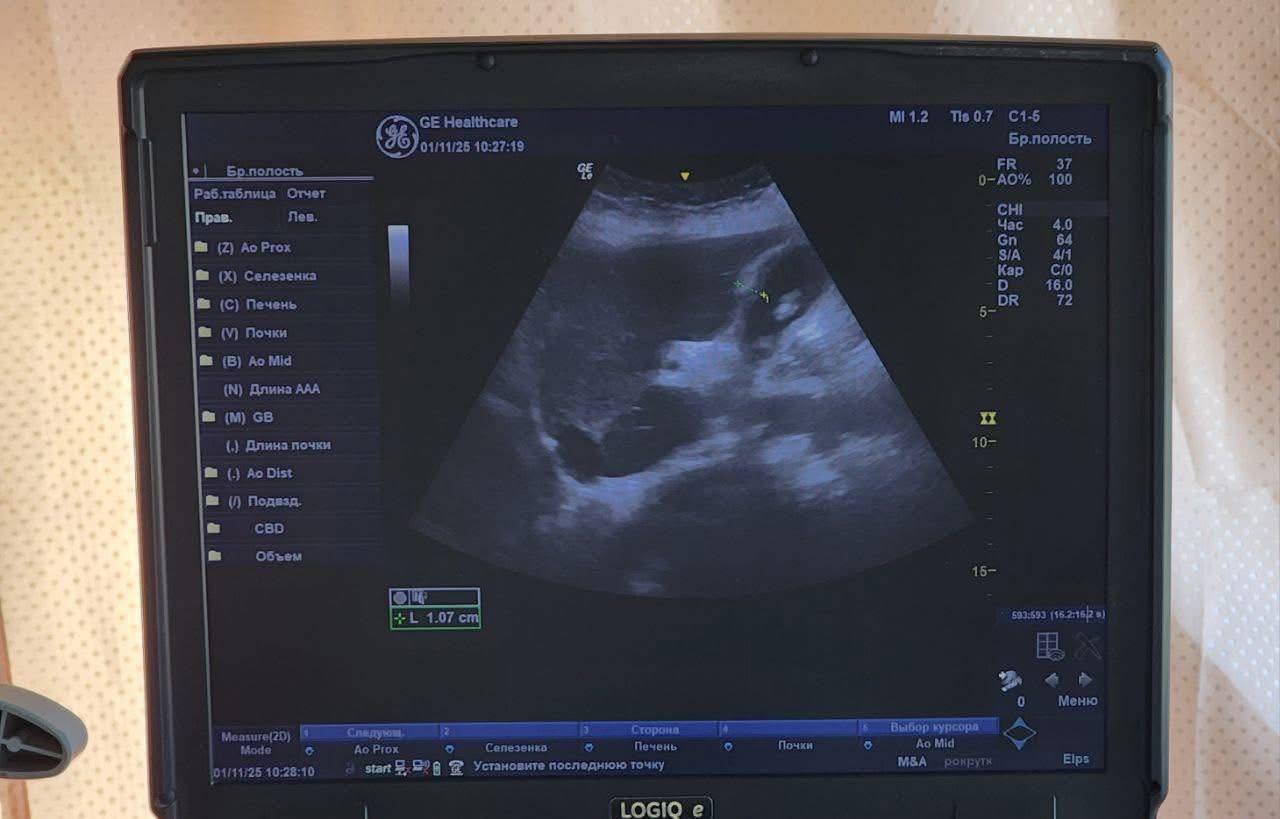

Медична команда стартувала у селі Новокарбівка. Місцеві жителі змогли отримати консультації хірурга та гінеколога, пройти УЗД, ЕКГ, а також здати лабораторні аналізи — загальний, біохімічний, коагулограму та цитологічні мазки. Загалом медики оглянули 72 людини, з яких 25 отримали адресну допомогу — медикаменти, вітаміни та засоби гігієни.